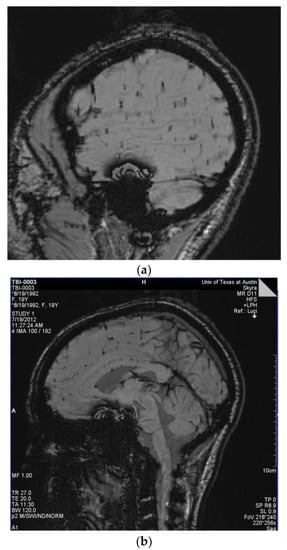

Figure 3.

(a) Players 29 and 16: Susceptibility-weighted imaging (SWI) demonstrating multiple small areas of signal loss in the base of the sulci. Paramagnetic compounds including deoxyhemoglobin, ferritin, and hemosiderin from the hemorrhages distort the magnetic field resulting in the signal loss. These images are consistent with a primary site of vascular injury and bleed into the brain parenchyma at the base of the sulci; (b) SWI Image of Player 12 demonstrating multiple small areas of signal loss in the base of the sulci. Paramagnetic compounds including deoxyhemoglobin, ferritin and hemosiderin from the hemorrhages distort the magnetic field resulting in the signal loss.